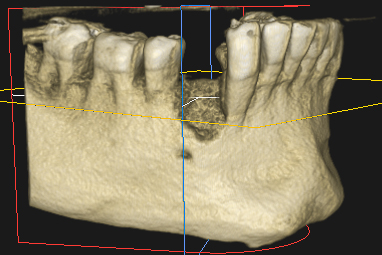

1. Estudio inicial con TAC 3D

Se analiza la cantidad y calidad del hueso para determinar la técnica de injerto más adecuada y planificar el procedimiento con precisión.

En todos los casos, un estudio inicial con TAC 3D es imprescindible para determinar la viabilidad del injerto y elegir la técnica más segura y eficaz.